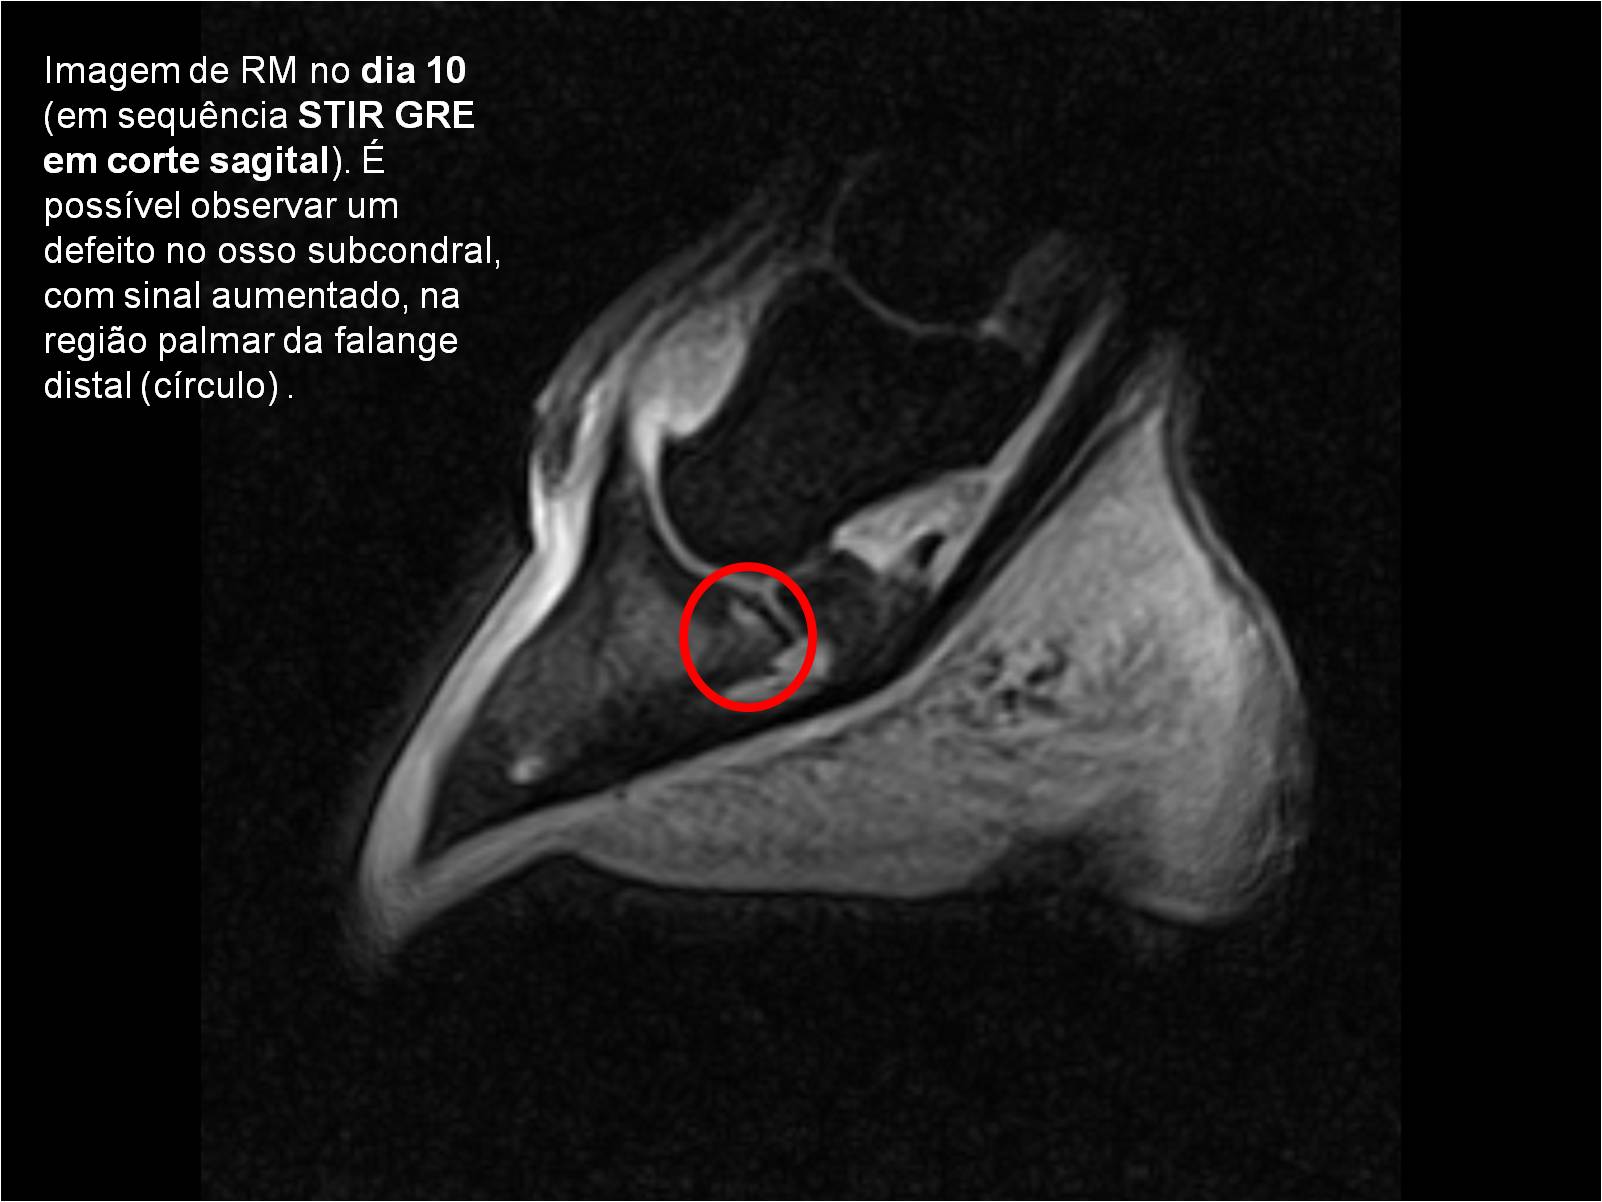

Publisher: Universidade de Évora

Abstract: O relatório de estágio encontra-se estruturado em três partes distintas. A primeira parte faz a caracterização das infraestruturas e funcionamento do Hospital Veterinário de Equinos de Lüsche, Oldenburg, Alemanha, assim como a análise casuística dos casos clínicos acompanhados durante os 6 meses de estágio. A segunda parte consiste de uma revisão bibliográfica sobre quistos do osso subcondral em equinos. Por fim, a terceira parte consta da apresentação e discussão de um caso clínico, nomeadamente o diagnóstico e acompanhamento imagiológico, por ressonância magnética, de um quisto subcondral na terceira falange num cavalo adulto; ### Abstract Equine Practice- Subcondral bone cyst of the third phalanx This internship report is divided in three parts. The first part characterizes the infrastructure and function of the Equine Hospital Lüsche, Oldenburg, Germany, as well as the casuistic of the clinical cases accompanied during the 6 month internship. The second part consists in a bibliographic review of cystic lesions of the subchondral bone in equines. The third part consists in a case report, the diagnostic and imagiological accompaniment, by use of magnetic resonance imaging, of a subchondral bone cyst in the distal phalanx of an adult equine.